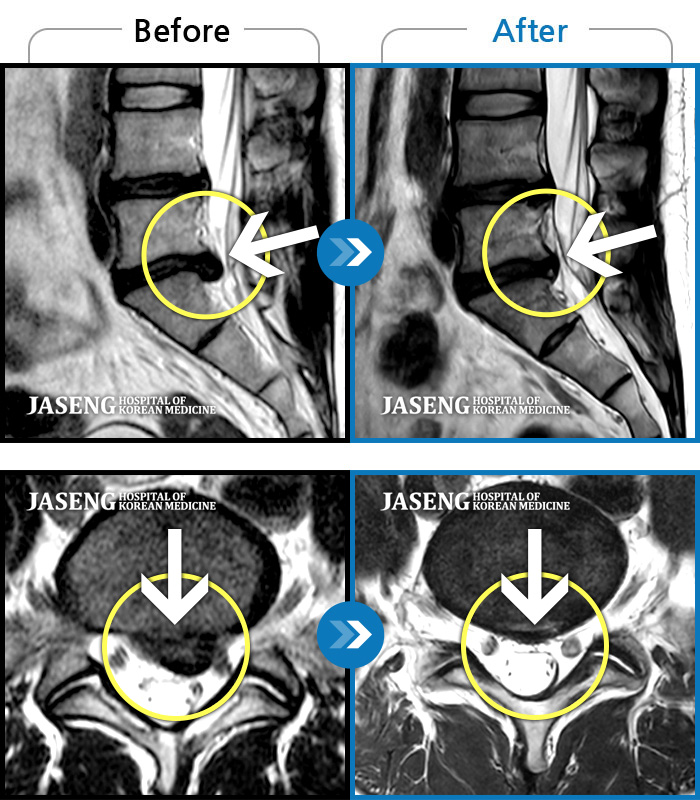

Before

After

환자에게 사전 동의를 받아 동일 조건에서 촬영되었습니다.

개인에 따라 치료 후 부작용이 발생할 수 있으니 의료진과 상담 후 치료를 진행하시기 바랍니다.

허리 통증과 함께 발끝 저림이 1년 이상 되었으며 최근 1-2개월 사이에 증상이 급격히 심해져 우측 다리 앞 뒤가 당기고 힘이 빠져 본원에 내원함

양측 허리 통증과 좌측 허벅지부터 발바닥까지 송곳으로 찌르는 듯한 통증 지속되어 내원하셨습니다.